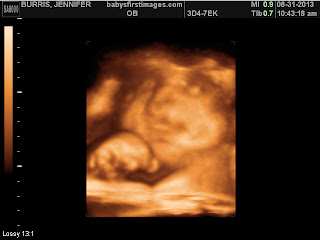

Ultrasound re-do!! YAY! I totally prepared for this one. Drank a cup of coffee on the way, ate breakfast, and drank OJ just before we got there. My mom came with m y niece and he did PERFECT! We got some really good pictures of his chubby little face, found out he has HAIR!!!! And confirmed 100% he is a HE! Oh, and he's a thumb/ fist sucker already! Just like my Niece, Katie, would not get that hand out of his mouth!! LOL I know we did the 3D late and could have waited to see the real thing, but it was so worth it to get a sneek peek of what we are expecting! To get a little taste of his personality already, beyond words. Definitely worth the money :)